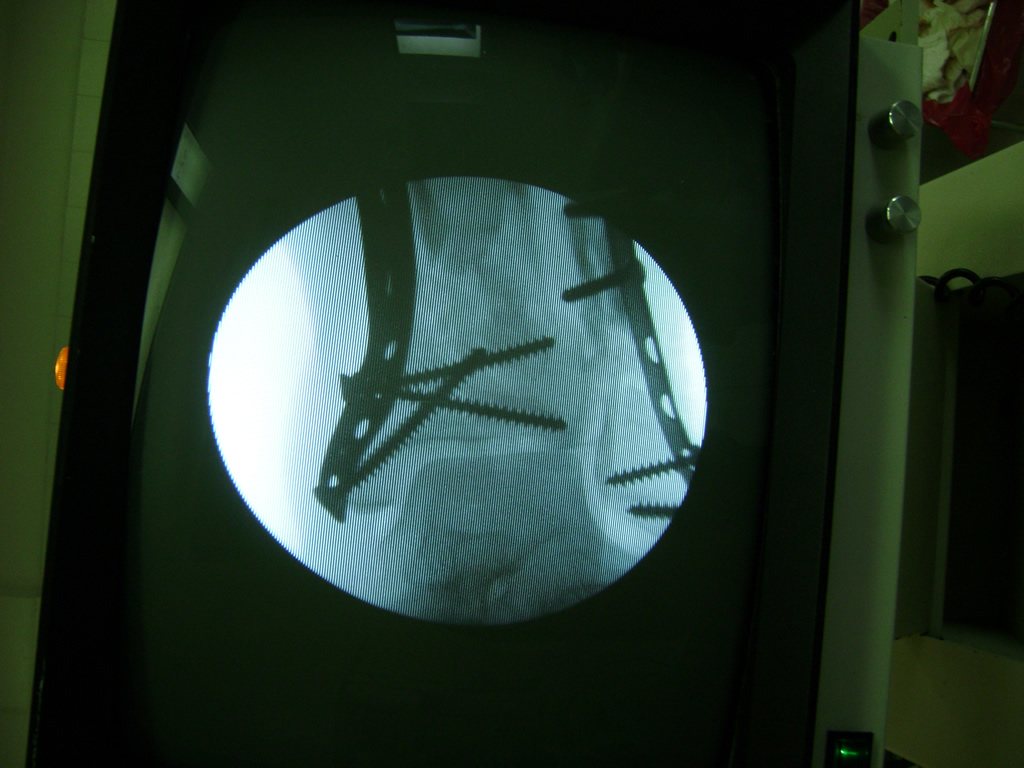

Cuando se necesita cirugía, es probable que esta implique el uso de clavijas de metal, tornillos o placas para sostener los huesos en su lugar mientras la fractura se consolida. Los elementos de soporte pueden ser temporales o permanentes.

Cirugía de Tobi...

Detail Download